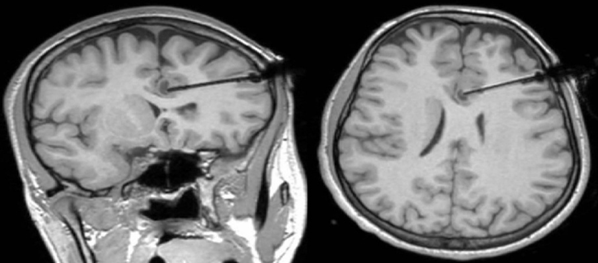

3. Laser Interstitial Thermal Therapy (LITT)

Fig 7: laser interstation thermal therapy (LITT) is a minimally invasive surgical option for pediatric epilepsy where a laser is used to destroy the specific brain tissue causing seizures.